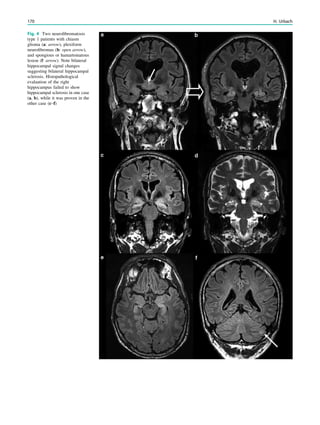

Fig. 2 Epileptogenic lesion and symptomatogenic zone. A 40-year-

old woman suffered from complex focal seizures with a fearful face

and body rocking. The symptoms thus pointed to the mesial frontal

lobe as the origin. MRI shows right-sided hippocampal sclerosis

(a, arrow). Simultaneous video and EEG recordings from interhemi-

spheric (c) and convexity strip and intrahippocampal depth (b) elec-

trodes show seizures starting in the right hippocampus (d, arrow).

Clinical symptoms start around 1 s afterwards (d, asterisk)

22 H. Urbach